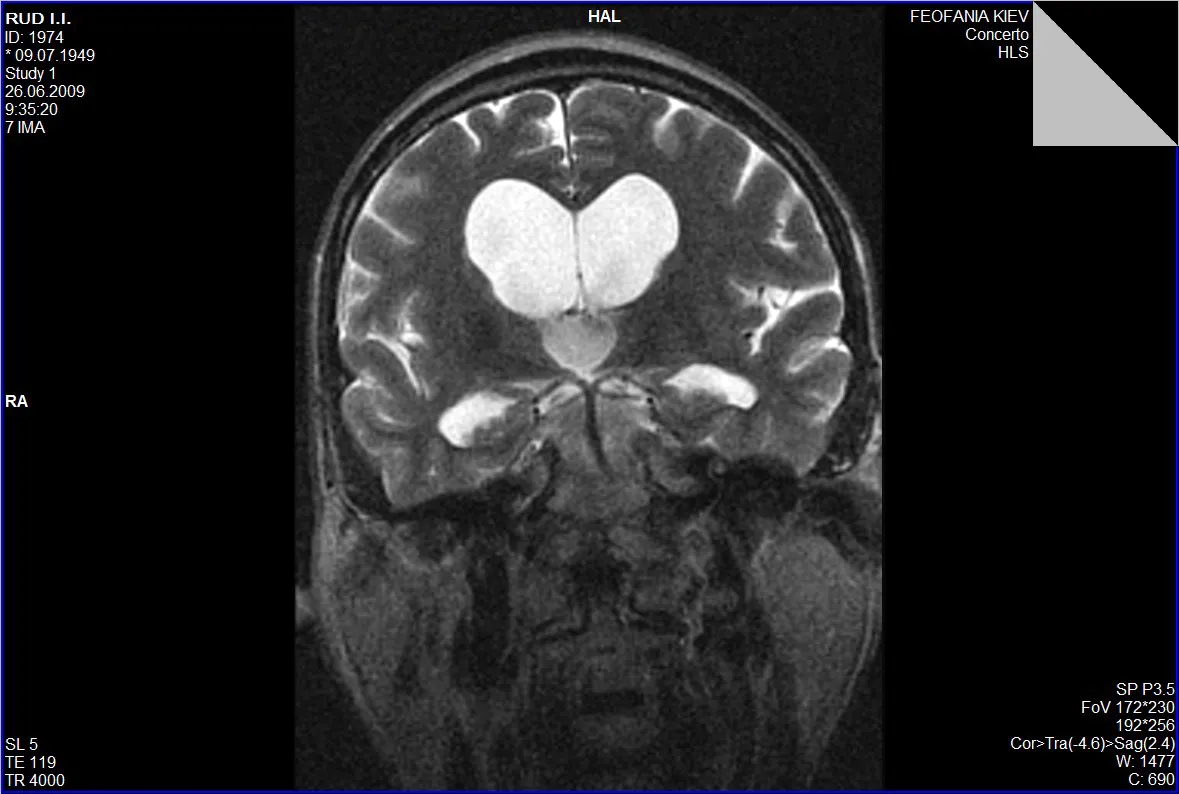

Гідроцефалія, або водянка головного мозку, — це патологічний стан, який характеризується накопиченням цереброспінальної рідини (ліквору) у шлуночках мозку та міжоболонкових просторах.

Звернутися з метою обстеження та верифікації діагнозу гідроцефалії із наступним нейрохірургічним втручанням ви можете Центрі Нейрохірургії «Оберіг». До переліку обстежень входить стандартний лабораторний пакет загальноклінічних аналізів та МРТ головного мозку.

Основним методом нейрохірургічного лікування є шунтування шлуночків мозку, однак в Центрі нейрохірургії впроваджена авторська методика керівника Центру Андрія Данчина, яка передбачає мікрохірургічне ендоскопічне втручання із формуванням отворів у стінках шлуночків для безперешкодного лікворообігу, що успішно використовується вже понад десятиліття та позбавляє пацієнта від необхідності регулярних операцій по заміні шунтів.